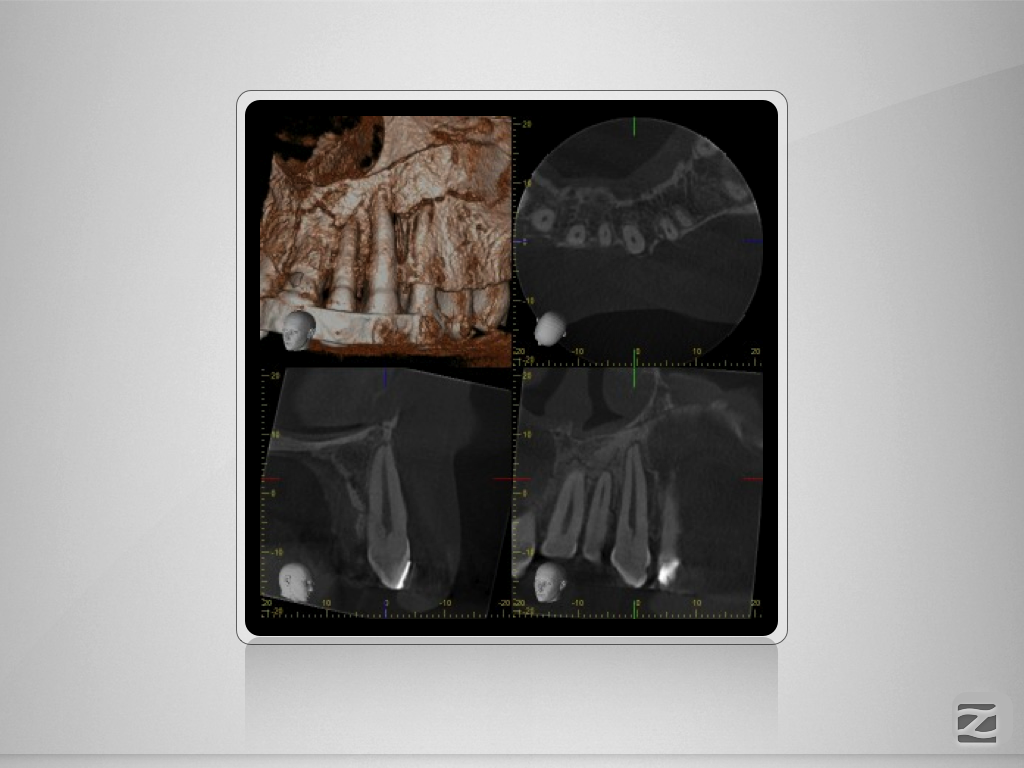

Multitrauma D.014

Mehrfach-Trauma